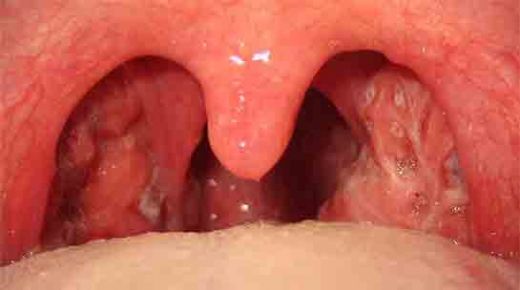

Sol Bademcik Şişmesi: Belirtileri ve Tedavisi

Sol bademcik şişmesi, genellikle boğazın arka kısmında yer alan lenfoid dokunun iltihaplanması veya enfekte olması durumudur. Bademcikler, bağışıklık sisteminin bir parçası olarak, vücut savunmasında önemli bir rol oynamaktadır. Bu durum, çeşitli etkenlerden kaynaklanabilir ve genellikle enfeksiyon belirtisi olarak ortaya çıkar.